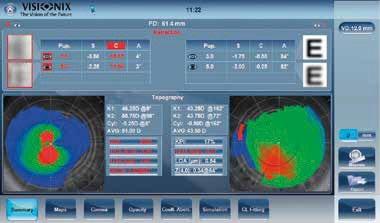

Non-Contact

Occular

Corneal

Scheimpflug

Has establishing a dry eye clinic been on your ‘to do’ list for some time now?

If the answer is a resounding ‘YES’ then you are not alone and this year’s Independents Day is definitely for you! This year’s programme is focussed on the pros and cons of commercialising dry eye services. The programme will be thought provoking, delivering useful tips and great ideas from top speakers who have ‘walked the talk’.